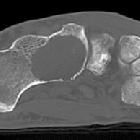

Pseudotumor

des Kalkaneus: An typischer Stelle zeigt sich eine zystoid imponierende Rarefizierung der Spongiosa Struktur im Calcaneus. Differenzialdiagnostisch wäre ein Calcaneus Lipom denkbar, dieses hat jedoch häufig eine zentrale Verkalkung.